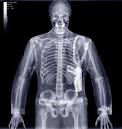

Desde que Wilhelm Röntgen descubrió que los rayos X permiten captar estructuras óseas, se ha desarrollado la tecnología necesaria para su uso en Medicina.

La radiología es la especialidad médica que emplea la radiografía como ayuda de diagnóstico, en la práctica, el uso más extendido de los rayos X.

Los rayos X son especialmente útiles en la detección de Enfermedades del Esqueleto, aunque también se utilizan para diagnosticar enfermedades de los tejidos blandos, como la neumonía, el cáncer de pulmón, el edema pulmonar, los abscesos.

En otros casos, el uso de rayos X tiene más limitaciones, como por ejemplo en la observación del cerebro o los músculos. Las alternativas en estos casos incluyen la tomografía axial computarizada, la resonancia magnética o los ultrasonidos.

Los rayos X también se usan en procedimientos en tiempo real, tales como la angiografía, o en estudios de contraste.